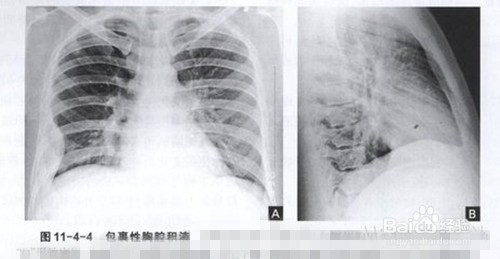

5、X线检查 胸部积液,检查发现患侧肺部呈大片密度均匀一致阴影。